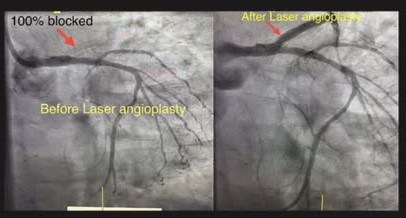

Apollo Hospitals, Chennai, has set a new standard in complex cardiac care by successfully treating two high-risk coronary cases. Leveraging the advanced CHIP (Complex High-Risk Indicated Procedure) technique and ELCA (Excimer Laser Coronary Angioplasty), the institution reaffirms its leadership in addressing complex coronary blockages with precision, innovation, and patient-centric expertise.

The team reopened a completely occluded 12-year-old stent using laser angioplasty, restoring blood flow in a challenging, long-standing blockage. In the second case, a 15-year-old stent with severe restenosis and an ejection fraction of just 30 percent required a tailored, high-risk intervention. Supported by IABP (Intra-Aortic Balloon Pump) and ELCA laser therapy, the team successfully cleared the blockage and placed a new-generation stent. Both patients made excellent recoveries and were discharged within 48 hours.